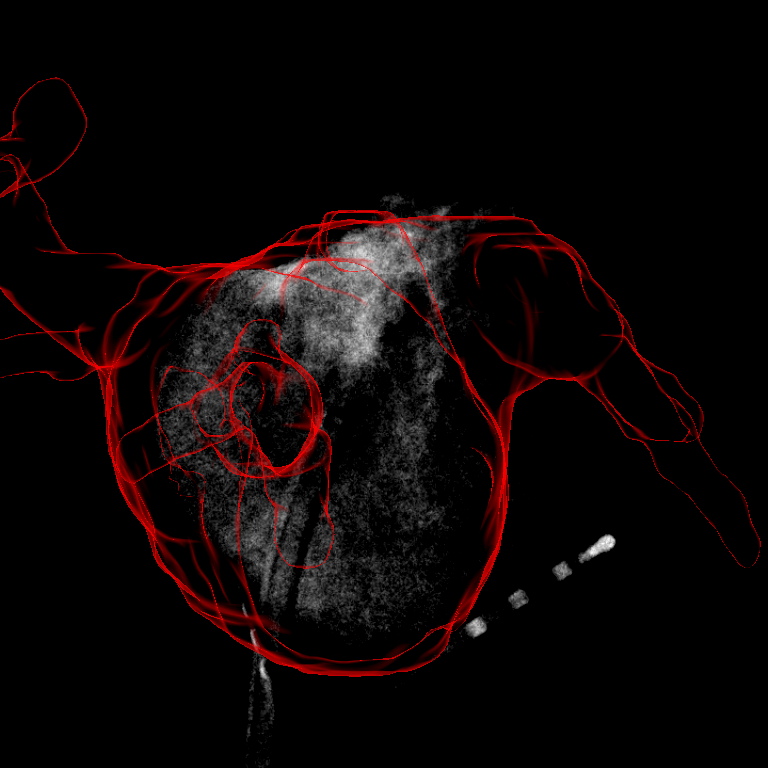

Refer to caption

Figure 1: A correct (red) and wrong (cyan) registration result. In both cases, the contrasted area is fully inside the projection shadow represented by the colored outline. This leads to a similar NCC value when using only an area-based feature for automatic registration. Thanks to the best reference frame selection, motion artifacts could be kept to a minimum. Only some remained in the vicinity of the moving coronary sinus (CS) catheter and the diaphragm, see white arrows.